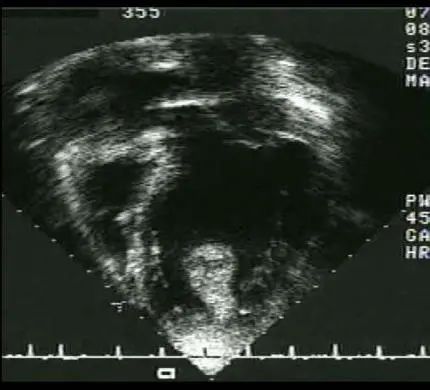

此培训为MAYO诊所推出的心内科fellow系列培训之一,主要目的是能够使大家学习到AMI以后心脏机械并发症的识别和诊断,还有ACS的非心脏的并发症的表现,以及临床中存在与ACS临床上有相似之处的非心脏疾病。 急性心肌梗死后出现的并发症,分为心脏性和非心脏性的,心脏并发症又包括心电学方面的并发症以及机械并发症,非心脏性并发症包括血栓栓塞和出血,还可能出现与心包相关的并发症。 心脏机械并发症包括就是破裂性和非破裂性的2类,破裂性并发症包括游离壁破裂、室间隔穿孔和乳头肌断裂,其中游离壁破裂既可能是直接的穿孔,也可以是亚急性破裂形成假性动脉瘤这样包容性的破裂。而非破裂性机械并发症包括严重的左室心力衰竭,右室梗塞,左室壁动脉瘤以及缺血性二尖瓣反流。 从根本上来说,这些严重并发症的发生都与心脏的泵功能衰竭有关,泵功能的衰竭造成了血流动力学不稳定以及基线的电不稳定性。 第一节:非破裂性机械并发症 非破裂性机械并发症,即严重的左室心力衰竭——心源性休克,右室梗塞,左室壁动脉瘤以及缺血性二尖瓣反流。 1、 心源性休克:在心梗发生时,发生心源性休克的主要原因就是大面积的心肌梗死,那么如果要导致心脏泵功能衰竭,左室心肌质量至少要损失40%以上。其他导致心源性休克的原因还有右室梗塞、心脏破裂以及快速和缓慢性心律失常。 2、 右室梗塞:也是导致心源性休克发生的重要原因。在下壁心梗的患者中,大概有33%的患者同时也发生右室梗死,这种情况多见于RCA近端闭塞,与高死亡风险相关。在所有下壁STEMI者中都要考虑是否同时存在RV梗塞,心电图V1和RV4导联ST段抬高超过1mm为其特异性心电图改变(图1)。 图1. 右室梗塞的心电图表现 3、 右室梗塞为什么会导致患者发生心源性休克呢?从病理生理上讲,右室急性缺血时会致其收缩不良,导致RV每搏输出量和峰压降低,继而是左室前负荷降低,心输出量降低;另一方面,急性缺血还同时使右室舒张功能受损,此时右心充盈压显著增加,并且由于右室急剧扩张,会在心包内占据很大体积,使得心包内压力显著增加,这些综合造成的结果使RV和LV的充盈减少。左心充盈压下降而右心压力不断升高,最终导致低血压、肺血流减少、颈静脉压升高,其临床结果可能类似于心包填塞以及缩窄性心包炎。 4、 左室壁动脉瘤(图2):首先提出一个问题供大家思考,以下有关左室壁动脉瘤的说法哪一个是正确的?1左室壁动脉瘤只局限于心内膜下;2有一个相对狭窄的颈部;3是否都与前壁心梗有关;以及4容易有血栓的附着,并且心包是组成瘤壁的一部分。实际上,左室壁动脉瘤在STEMI后的发生率<5%,前壁梗死的患者更易发生,及时进行再灌注治疗可以降低其发生率。它突出于心腔外侧,瘤壁就是左室壁,颈部和底部的比例大约是1:1,可以出现附壁血栓。所以上述说法中只有3是正确的。 图2. 左室壁动脉瘤示意图,O;颈部,D:底部,LA:左心房,LV:左心室,AO:主动脉 5、 缺血性二尖瓣反流:为心梗后左室重构所致,表现为乳头肌移位、乳头肌功能不良使瓣叶活动受限以及瓣环扩张(图3)。治疗的焦点集中于及时的再灌注治疗、利尿剂的应用和后负荷的降低,如果遗留严重的二尖瓣反流,则会导致心梗后的远期生存率下降。 图3. 瓣环扩张(A)、乳头肌功能不良致瓣叶活动受限(B)导致大量MR 第二节:破裂性机械并发症 破裂性并发症包括游离壁破裂、室间隔穿孔和乳头肌断裂,其中游离壁破裂既可能是直接的穿孔,也可以是亚急性破裂形成假性动脉瘤这样的包容性破裂。大多数破裂性并发症都发生在AMI的第一个24小时之内,剩余的则发生在1周之内。通过超声心动图可以发现MI的机械并发症,包括急性乳头肌断裂、下段室间隔断裂、上段室间隔断裂以及二尖瓣脱垂。 1、 乳头肌断裂所致二尖瓣反流(图4):乳头肌断裂常发生在MI后的2~7天,急性缺血事件发生时,从心外到心内的压力梯度增加,心内灌注降低,乳头肌属于心内结构,缺血的敏感性增加。一旦出现需要外科手术治疗。 图4. 乳头肌断裂(箭头所示) 2、 室间隔缺损(图5):属于MI后的罕见并发症,多于梗死后3~5天发生,在梗死后即刻或者第一个24小时内就可以发生,部分与患者进行的纤溶治疗有关。由于再灌注治疗的开展,目前发生率已经由2%降至0.2%。破裂发生在健康心肌和坏死心肌的交界处,在前壁心梗时,缺损位于室间隔心尖部,下壁心梗时缺损则位于下-后间隔基底段,RV梗死及功能失常者预后不良。 图5. 前壁心梗(A)、下壁心梗(B)所致不同部位室间隔穿孔 3、 游离壁破裂:急剧的、常为致死性机械并发症;发生率<1%;MI后死亡约8~24%是由此而造成;通常在梗死后的5天内发生。好发因素包括1首次心梗,2前壁心梗,3老年患者以及4女性。 4、 亚急性破裂:是一种特殊类型的游离壁破裂,占所有游离壁破裂患者的约1/3,是因为附壁血栓和心包覆盖了穿孔部位所致,局部表现为假性动脉瘤(图6),临床上常比较隐匿,并且可能仅通过UCG发现,因此任何超声发现的心脏周围局部积液都需要引起怀疑并详细扫查。与真性动脉瘤(即左室壁动脉瘤)不同,假性动脉瘤的颈部狭窄,颈部与底部的比值<0.5,心包是瘤壁的组成部分。亚急性破裂的进展常是难以预测,可以进展至完全破裂乃至心包填塞,因此需要外科治疗。 图6. 左室假性动脉瘤示意图,O;颈部,D:底部,LA:左心房,LV:左心室,AO:主动脉 第三节:AMI的非心脏并发症 AMI的非心脏并发症主要包括血栓栓塞和出血,以及心包并发症。那么下面关于左室血栓的说法哪个是正确的呢?1下壁心梗更为常见,2如果不予治疗栓塞风险可达50%,3栓塞的风险取决于血栓的移动性和是否凸出于腔内。左室血栓常(图7)见于大面积前壁心梗,在再灌注前时代其发生率可高达40%,有再灌注治疗后这一几率已降至4~15%;经胸超声心动图是发现LV血栓的第一选择;心脏MRI的敏感性更高,但与超声心动图的特异性相似。由于心梗后不运动和运动障碍的室壁区域存在静止血流,因此如容易在局部形成附壁血栓。如果梗死部位为心尖部,且左室EF值减低达<30%,则存在血栓栓塞的高风险。如果未治疗,左室血栓发生栓塞的风险为10~15%,这一风险的高低还取决于栓子的移动性和是否突出于心腔内,早期且持续的抗凝治疗(3~4个月)可以降低栓塞风险。 图7. 左室心尖部附壁血栓 一图总结心脏机械并发症 第四节:类似ACS的非心脏疾病 通过一个有趣的病例,我们来学习一下在临床中可能存在类似于ACS表现的非心脏疾病。这是一个77岁老年女性,症状为头晕、恶心、呕吐,急诊CT除外了急性卒中,但心肌坏死标记物升高,心电图提示为Af、并且下壁前壁导联T波倒置,但超声心动图上仅表现为室间隔中下段至左室心尖部运动减低,没有看到下壁及前壁的运动异常。随后患者出现严重的高血压和心动过缓,并存在定向力、消化不良和眼球震颤,继续监测头CT及MRI,结果发现枕叶大面积脑梗。实际上,早在1947年,急性卒中所引起的ECG变化就已经被报道,病程中出现深大的倒置T波则被称为神经源性T波。在急性颅内事件发生时可以存在肌钙蛋白的升高以及心电图出现ST-T改变,在卒中的急性期,ECG诊断急性心梗的特异性会降低。 除急性脑血管病以外,以下疾病也会出现类似于ACS的临床发现,包括心电图异常和心肌坏死标记物升高,如特发性应激性心肌病,主动脉夹层,肺栓塞等等,需要及时进行诊断及鉴别诊断。 最后需要强调的是,超声心动图是发现AMI后心脏机械并发症的最重要检查,AMI发生后一周内必须行UCG检查以发现隐匿的高危并发症。